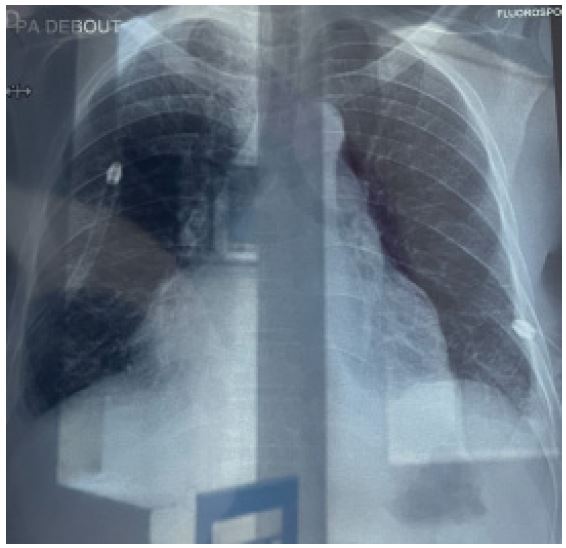

Figure 6: Showing associated bilateral moderate pleural effusion with lung atelectasis.

Figure 7: Showing clear pleural space after thoracic drains placed with good lung re-expansion.

Patient was placed under general anesthesia, intubated and placed in the supine position on the surgical bed. Routing disinfection and surgical prepping was done. A subxiphoid median incision starting from xiphoid process to about 7 cm inferiorly was made. Subcutaneous and muscle fascia dissected and the xiphoid process amputated for better exposure of the pericardium. The bulging pericardium seen with a pericardiotomy made gently on the pericardium. Approximately 2 Liters of serohematic pericardial fluid was drained and a pericardial drain was placed in the pericardial space and connected to a self-expanding vacuum drain which was intended to drain the rest of the pericardial fluid. A biopsy of the pericardium was collected alongside 10cc of pericardial fluid and send for histo-cytology studies to determine the etiology of the effusion. Two thoracic drains were also placed and suture wounds closed up according to standard fashion and patient was taken to the surgical ward afterwards. Post operatively, cardiologist and infectious disease consults were requested for the patient. Post operative follow up was done. Histo-cytology results confirming TB as the etiology of the effusion. Patient was placed on anti TB medimedications by the infectious disease doctor and patient improved clinically and symptomatically with drained not producing anymore. Patient was later discharged 10 days post operatively and reviewed 2 weeks after with follow up cardiac echo and chest Xray not showing any pericardial effusion and pleural effusion respectively.